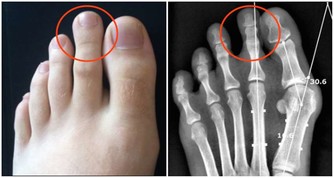

髕骨軟骨軟化的症狀

疼:上下樓會痛,膝關節突然打軟無力。有時候是半蹲發力時疼,尤其是搬重物的時候。嚴重的日常生活的活動中就會疼,走路的時候都有膝關節打軟腿的現象。另外,如果用手按摩髕骨的邊緣,常常有明顯壓痛。

響:膝關節屈、伸活動時,髕骨下面常常會出現響聲,嚴重的患者,自己坐著伸直腿,把手放在髕骨上,壓著髕骨摩擦一下,就能聽到“沙沙”的響聲,像關節裡面有沙子一樣。

腫:因為關節內部的炎症,導致關節滑膜分泌出很多液體,所以表現出膝關節腫脹。

細:髕骨軟化,會導致股四頭肌肌肉萎縮,疲軟、所以大腿外觀會變細。